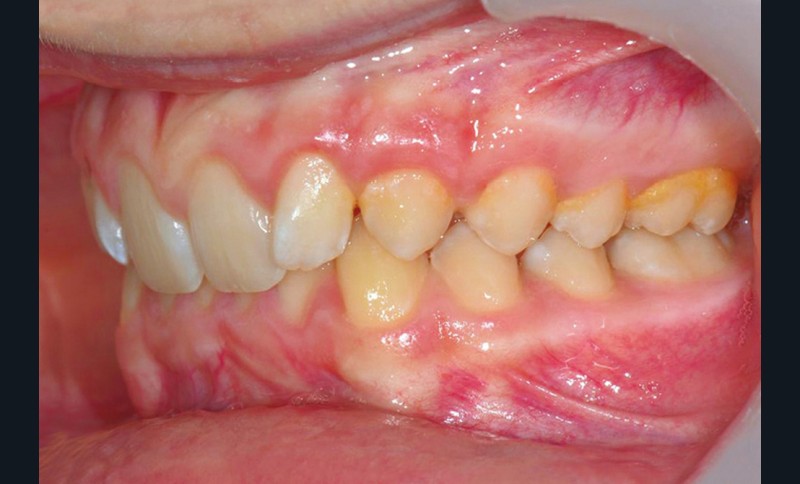

Son profil convexe s’inscrit dans un contexte de classe II squelettique par rétrognathie mandibulaire normodivergente sur un schéma de Classe II/2 avec supraclusion et encombrement modéré (fig. 1 à 7).

Le parodonte est de type 1 selon la classification de Maynard et Wilson.